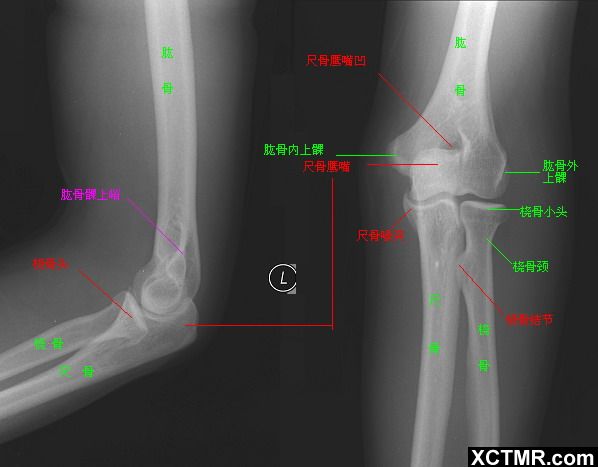

肘关节的X线解剖 肘关节常规X线片包括伸肘前后位及屈肘90°的侧位(图1)。正位像肱桡关节间隙清晰,呈下凹的浅弧形;肱尺关节间隙有尺骨滑车切迹重叠而变暗,呈上凹的弧形,故而正位片上肘关节间隙呈波浪状。屈肘侧位片,肱尺关节间隙清晰,呈半环形,前为冠突,后为鹰嘴。肱桡关节掌侧清晰,背侧部分和尺骨冠突相重叠。此时通过桡骨纵轴线的延长线也穿过肱骨小头中心。

伸肘正位片上,肱骨、尺骨长轴线形成向外165°~170°的夹角,此为生理性前臂外翻角,男性一般大于女性。若小于l65°叫肘外翻,大于190°叫肘内翻,如果是180°则叫直肘(图1-1),均属异常表现。肱骨长轴与尺骨长轴在内下方的夹角谓之提携角,正常范围5°~20°之间,女大于男。